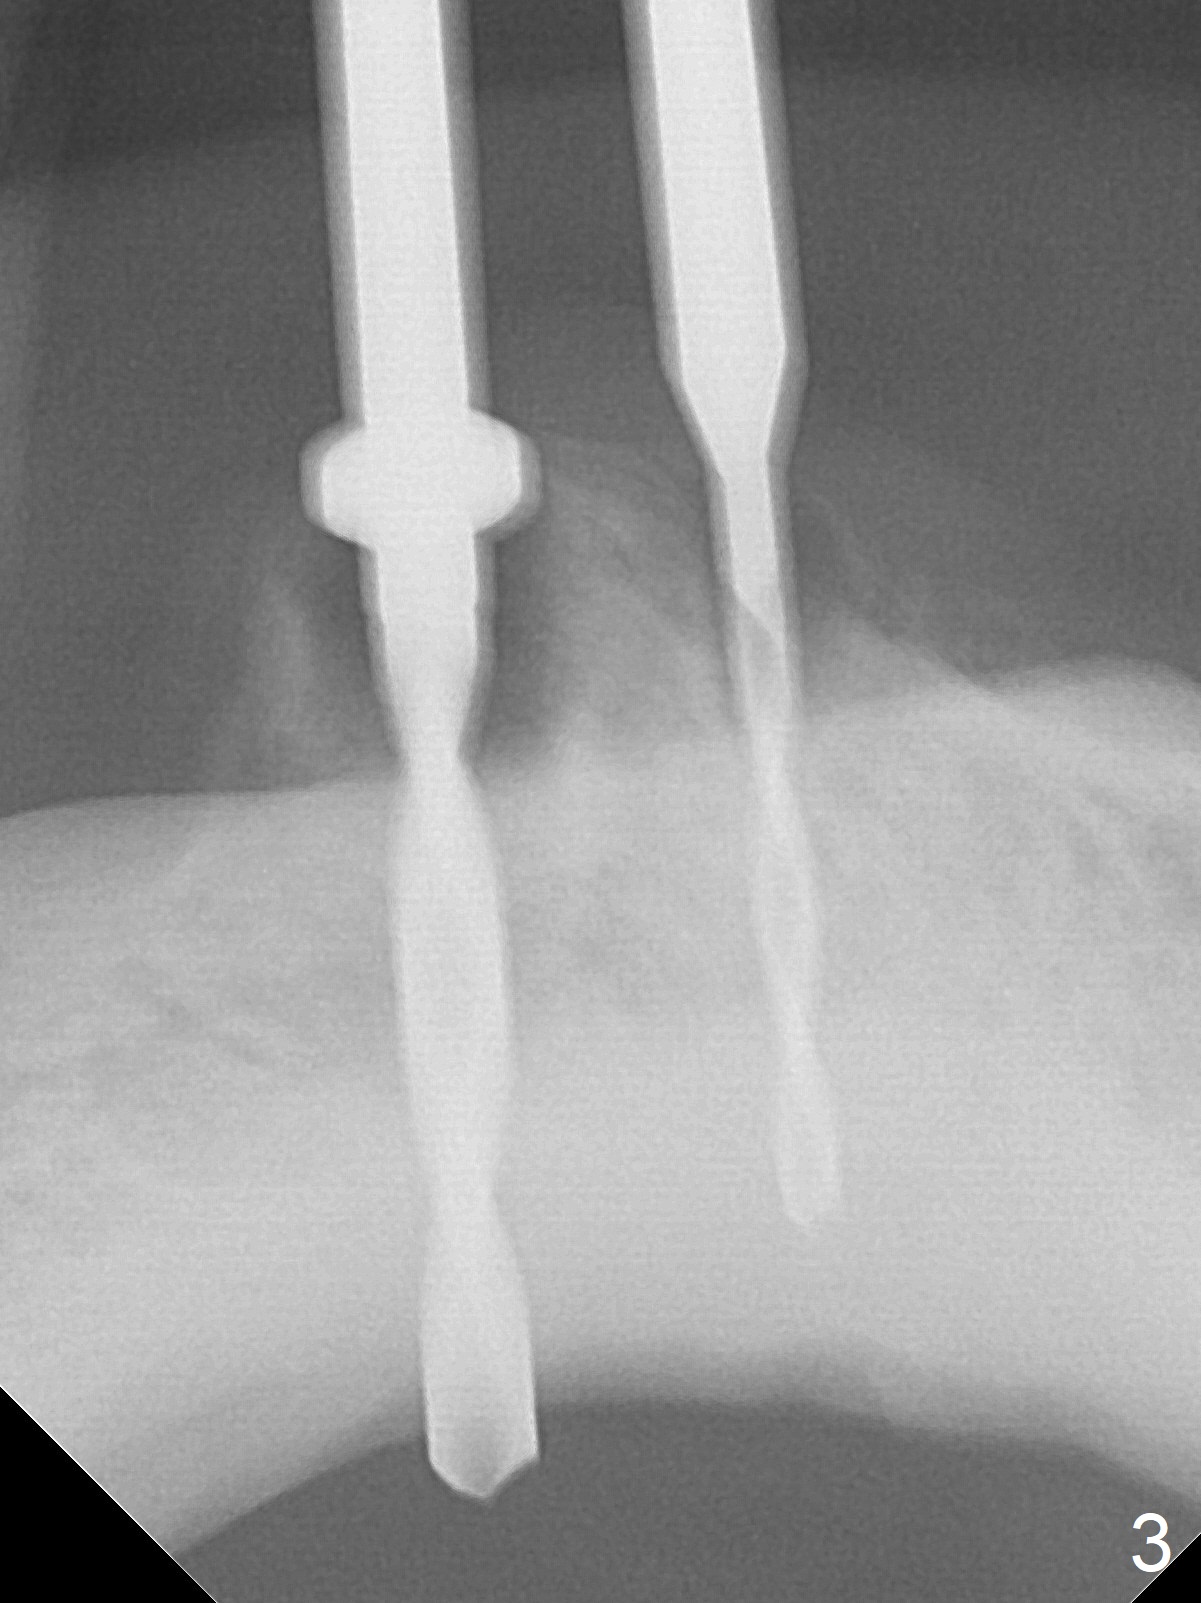

When the patient returns for #26 extraction and immediate implant and #27 RCT, it appears that the tooth #27 with subgingival margin distolingually is non-salvageable (Fig.1). She has dry mouth. Osteotomy is initiated in the lingual slope (Fig.4 red dashed line) of each socket with 1.2 and 2 mm drills for 16 and 19 mm at #26 and 27, respectively (Fig.2,3). The depth at #27 is subsequently reduced, while a 3x14(2) mm dummy implant is placed at #26 (Fig.5,6). A 3.8x13 mm implant is placed at #27 smoothly, while insertion of a 3x16(4) mm definitive implant (by mistake) has resistance (Fig.7). When the depth at #26 increases, there is feeling of perforation. The apex of the implant is truncated prior to reinsertion (Fig.8 >).